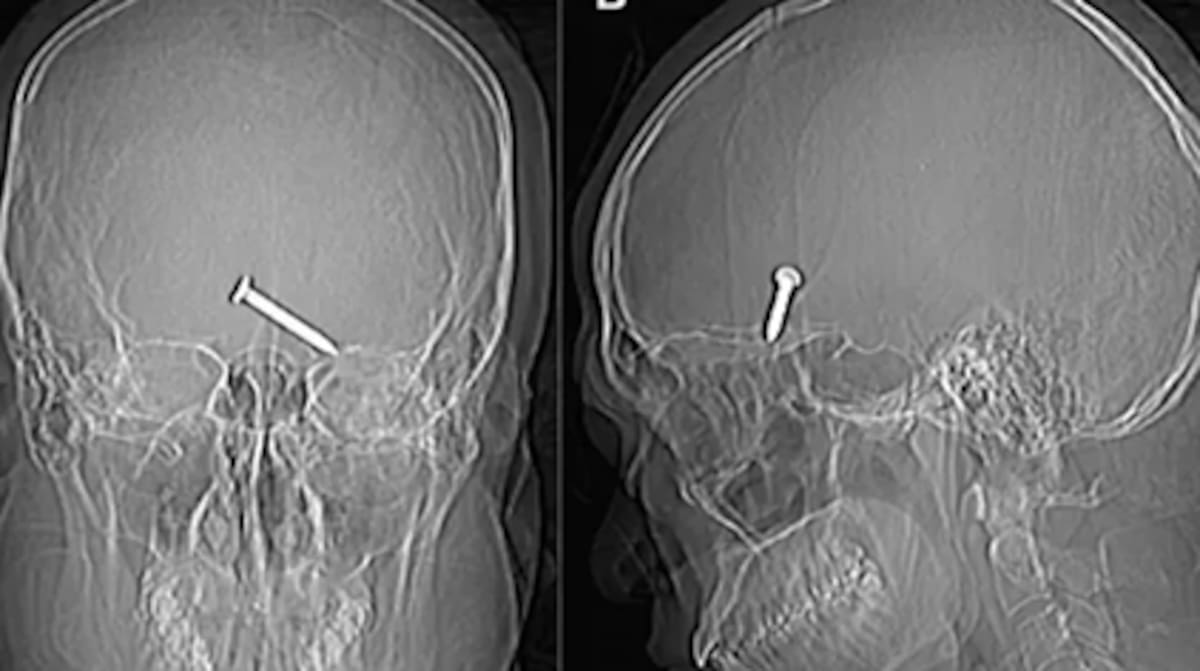

En un caso que ha llamado la atención mundial, un hombre de 30 años, cuyo identidad ni fue divulgada, se disparó por accidente con una pistola de clavos en la cabeza, reveló una revista médica de Malasia.

Tras el incidente, fue llevado de emergencia al hospital Sultanah Bahiyah de la ciudad de Alor Setar. Los médicos comprobaron que el clavo se había alojado en el lóbulo frontal del cerebro. Sin embargo, observaron que la herida no afectó nervios y arterias vitales dentro del cerebro.

De manera milagrosa, el hombre fue operado con éxito, ya que sacaron el clavo en una sola pieza. Después de extraer el tejido dañado en el accidente, curaron su párpado y cosieron la herida.